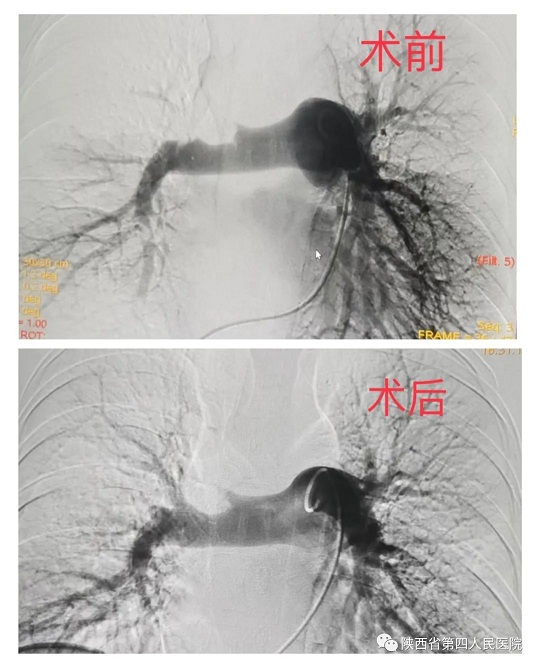

近日,六合彩生肖心血管内科专家团队成功救治了一名突发急性肺栓塞的患者。经充分评估病情后,为患者行急诊手术,通过医护人员准确、及时的救治后,患者转危为安。患者,年轻女性,37岁,因外伤骨折术后卧床40余天,活动后出现胸闷、胸痛、气短,及一过性意识障碍,家……